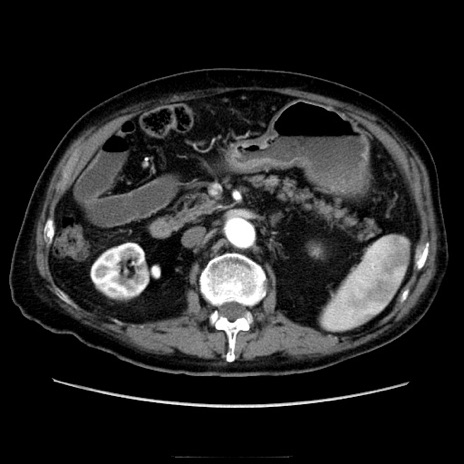

症例21(横断像)

【症例】70歳代男性

【主訴】腹痛

【現病歴】肝硬変・肝細胞癌にてかかりつけの方。約9時間前に食後より腹痛出現。症状が徐々に増悪し、嘔吐出現したため来院。

【既往歴】肝硬変、肝細胞癌(RFA、TACE後)

【身体所見】意識清明、表情苦悶様、BT 36℃、BP 129/78mmHg、P 88bpm、SpO2 97%(RA)、右上腹部から心窩部にかけて圧痛あり、反跳痛なし、筋性防御あり。

【データ】WBC 5800、CRP 0.16